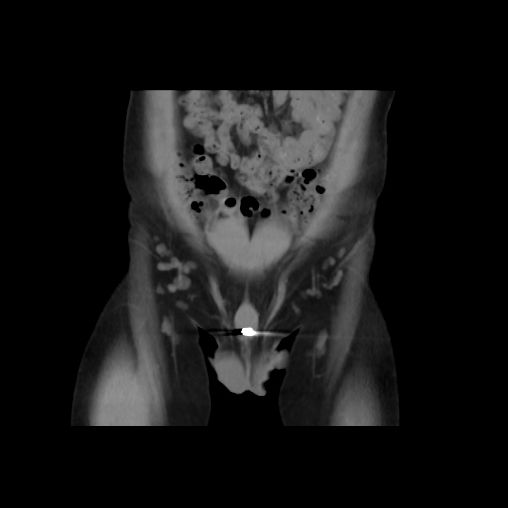

(尿道内的“金币”)

接诊后,考虑到异物为金属材质,且存留时间过长可能对身体造成特殊伤害,泌尿外科涂磊教授团队经过严密细致的讨论与准备,在全身麻醉下为童童实施膀胱镜尿道膀胱镜检+尿道异物取出术,一枚完整的“金币”被顺利取出。

泌尿外科副主任医师涂磊介绍,男性尿道长而细,存在2个生理弯曲及3个尿道狭窄处,异物进入后极易嵌顿,难以自行排出。及时取出膀胱尿道异物至关重要,若拖延至引发并发症后再治疗,会大幅增加诊疗难度。童童因为异物留滞2个多月时间,金属周围都长满了小结石,不仅造成尿道、膀胱局部损伤,也引发了童童的尿痛、尿急、血尿、排尿困难等症状,术后还需要一段时间的康复治疗。